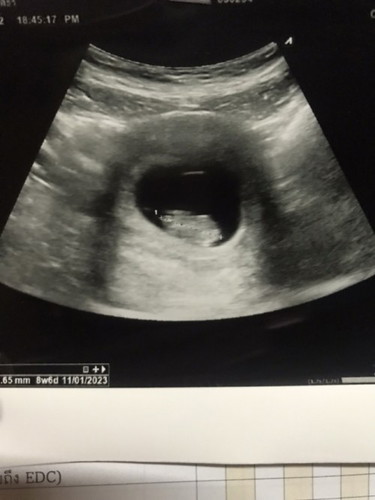

9 สัปดาห์แล้ว

ป้าหมอบอกเห็นตัวน้องแล้วนะ ตัวน้อยๆ แต่โตปกติดี หัวใจก็เต้นดีปกติ แข็งแรงดีด้วย แล้วอีก 1 เดือนมาเจอกันใหม่ 🥹